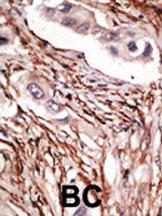

Supportive validation

- Submitted by

- Abcepta (provider)

- Main image

- Experimental details

- "Formalin-fixed and paraffin-embedded human cancer tissue reacted with the primary antibody, which was peroxidase-conjugated to the secondary antibody, followed by DAB staining. This data demonstrates the use of this antibody for immunohistochemistry; clinical relevance has not been evaluated. BC = breast carcinoma; HC = hepatocarcinoma."

- Primary Ab dilution

- 1:50~100